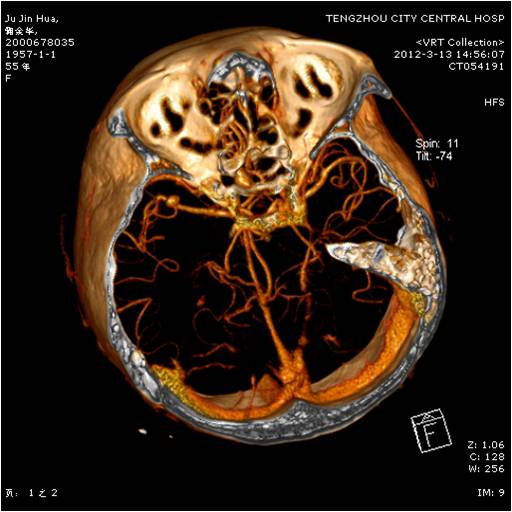

【手術(shù)圖片】

動(dòng)脈瘤夾閉術(shù)前 動(dòng)脈瘤夾閉術(shù)后